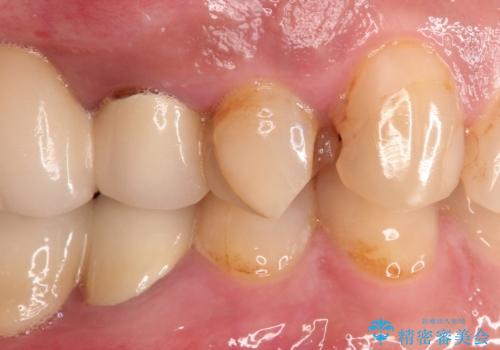

咬合力が強く、残存歯質が少ないためオールセラミッククラウンによる治療を行いました。

咬合力が強くかかる部分には欠けるリスクのほとんどない金属を用いることが最良ですが審美性に劣ります。

今回は白い材料での修復を希望されたため、欠けるリスクが高いセラミックインレーは避け、セラミッククラウンにて治療を行いました。